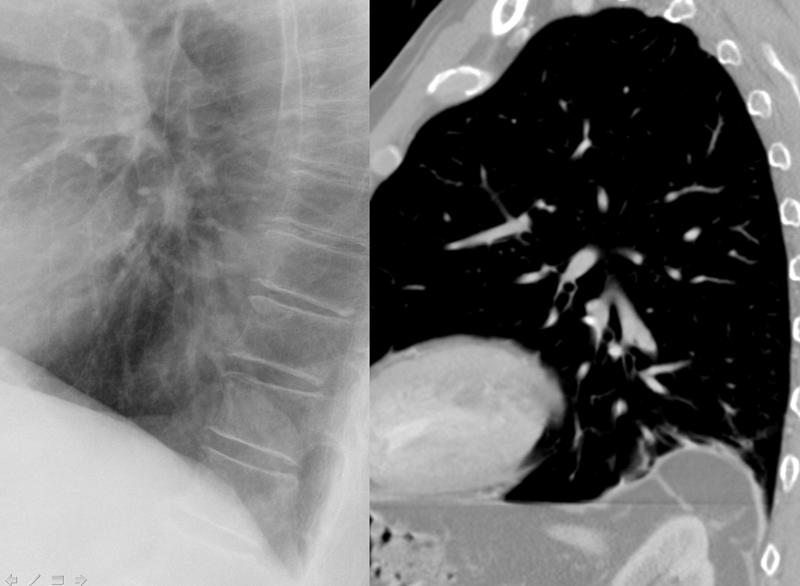

Congenital

Bochdalek hernia lat